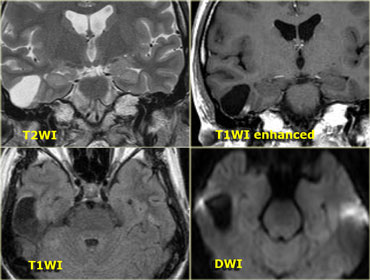

On the left some examples of tumors with a low signal intensity on T2WI.

1. Melanoma metastases have a low SI on T2WI as a result of the melanin.

2. GBM can have a low SI on T2WI because sometimes they have a high nuclear-cytoplasmic ratio. Most GBM's, however, are hyperintense on T2WI.

3. PNET typically has a high nuclear-cytoplasmic ratio. PNET is mostly located in the region of the 4th ventricle, but another, less common, location is in the region of the pineal gland.

4. Mucinous metastases can have a low SI on T2WI because they often contain calcifications..

5. Meningiomas are mostly of intermediate signal.

They can have a high SI on T2WI if they contain a lot of water.

They can have a low SI on T2WI if they are very dense and hypercellular or when they contain calcifications.